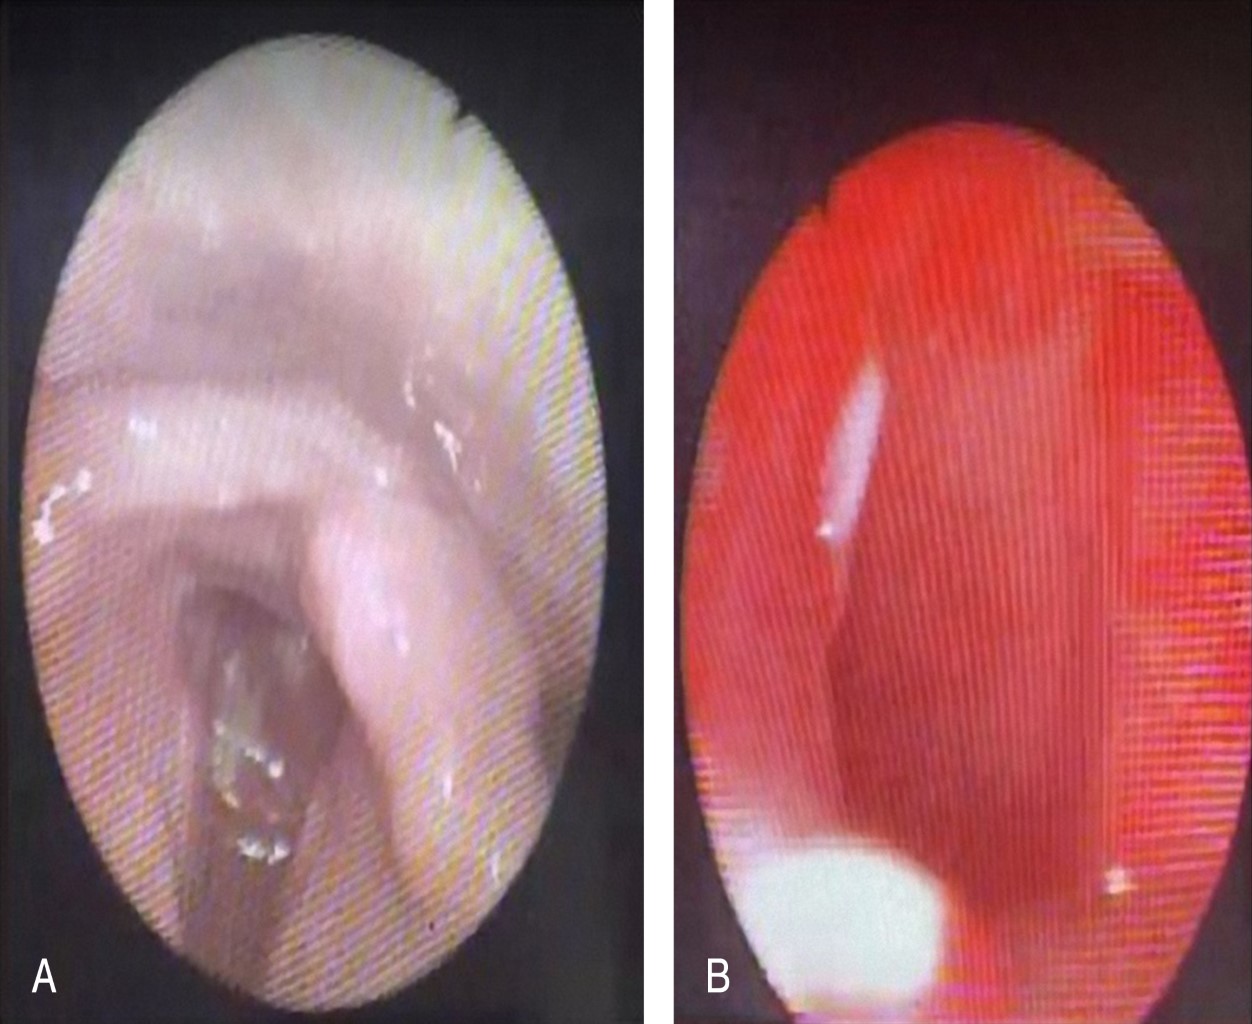

Figure 1